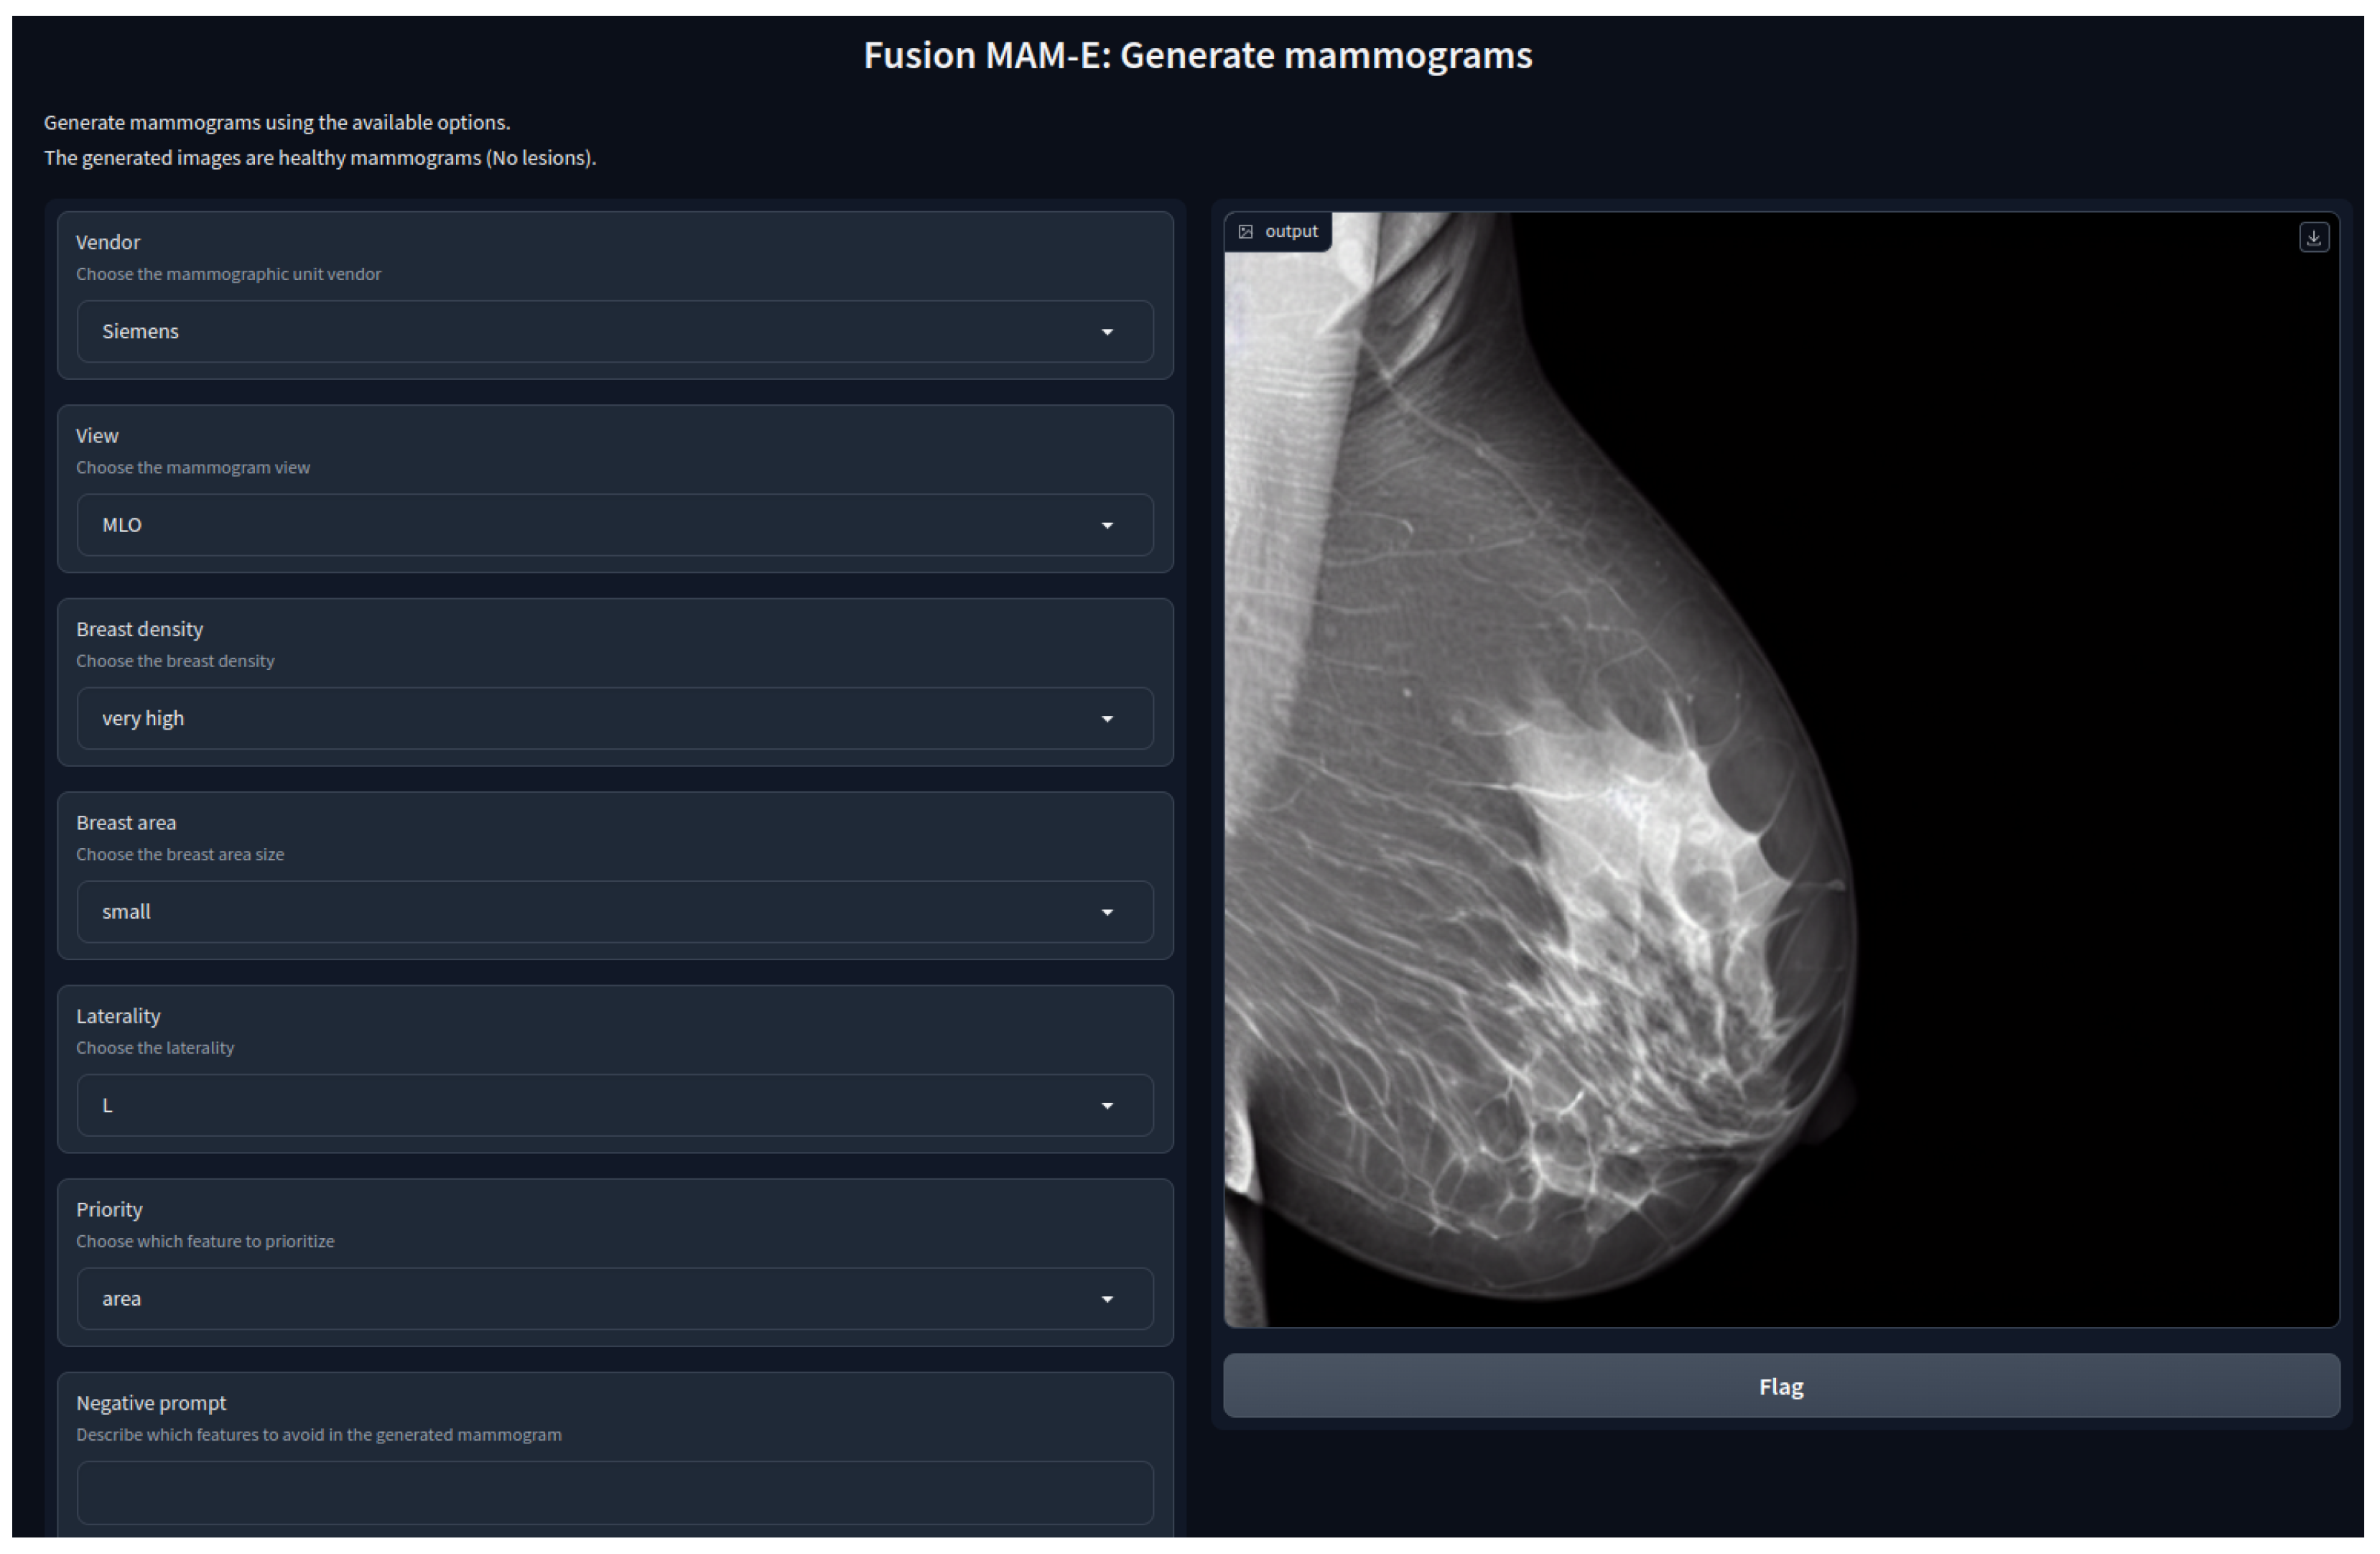

3.1.1. Conditional Models

3.3. MAM-E Graphical User Interfaces